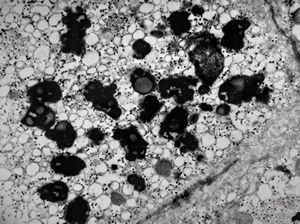

M,66y. | siderosomes

M,66y. | hemosiderin - siderosomes